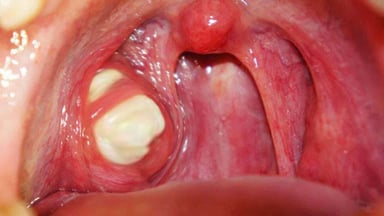

- Amidan sưng, tấy đỏ

- Các mảng trắng ở amidan

- Biến chứng tại chỗ: áp-xe amidan, viêm tấy quanh amidan…